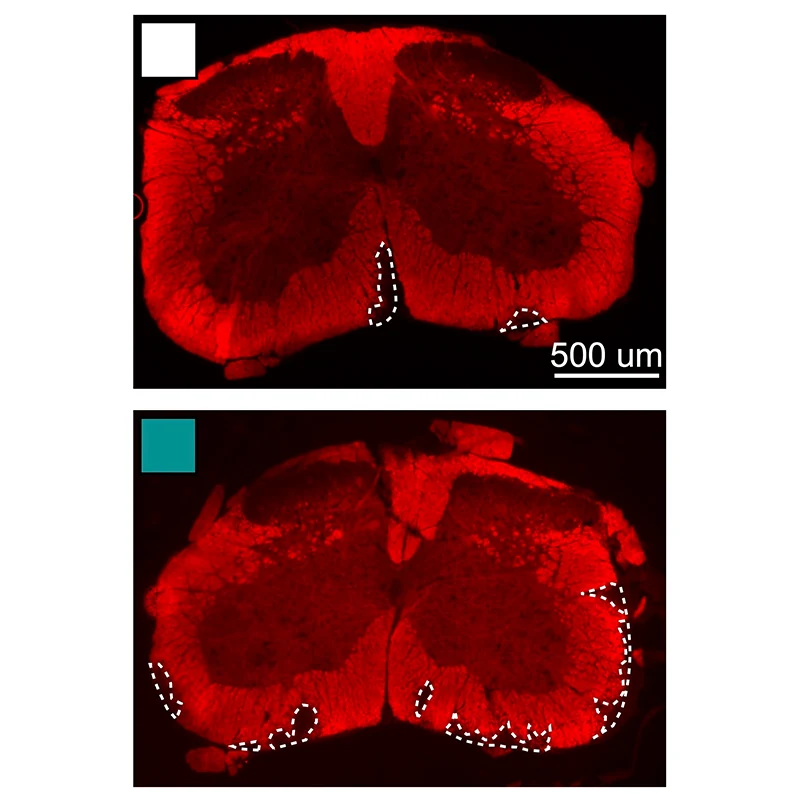

Demyelination in the spinal cord of a mouse with MS and cardiometabolic syndrome.